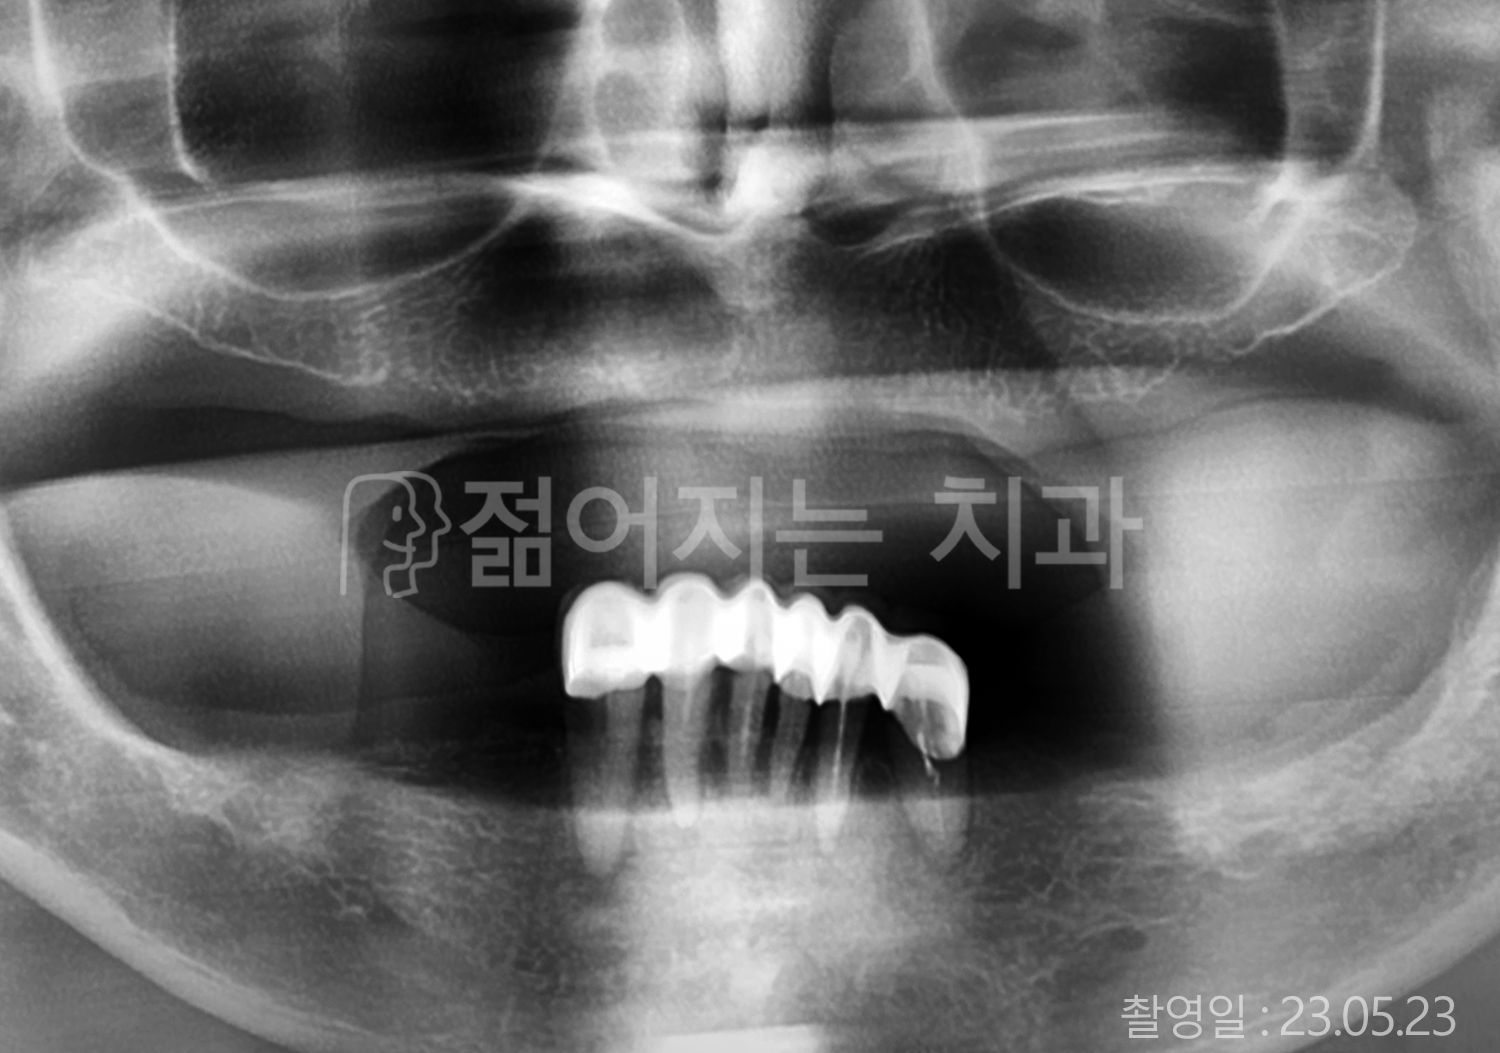

• 70대 고혈압, 당뇨 전체치아 10개 이상 임플란트

• 50대 고혈압, 당뇨 전체치아 10개 이상 임플란트

• 60대 고혈압, 당뇨 전체치아 10개 이상 임플란트

• 50대 전체치아 10개 이상 임플란트

• 70대 당뇨 전체치아 10개 이상 임플란트

• 80대 전체치아 10개 이상 임플란트

• 40대 전체치아 10개 이상 임플란트

• 60대 고협압, 고지혈증 전체치아 10개 이상 임플란트

• 60대 전체치아 10개 이상 임플란트